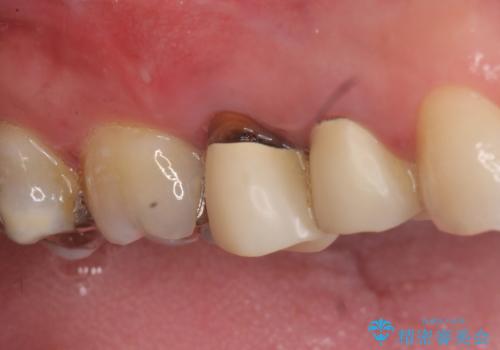

- 右上の奥歯でものを咬むと痛むので診て欲しいといらっしゃった方の症例です。

診査の結果、歯根が破折しており保存不可能だったため抜歯し、ブリッジによる補綴を行いました。